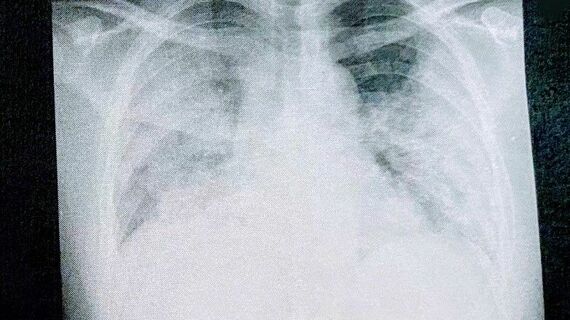

瀬川達也さん(仮名・37歳)はこの夏、コロナに感染し、医師に「死ぬかもしれない」と宣告を受けた。基礎疾患もなく、大きな病気をしたこともない男性だ。至って元気だったが、コロナ感染後に重症化。入院前には血中酸素飽和度が「72%」という極めて危険な数値にもかかわらず、苦しさの自覚症状がない「ハッピー・ハイポキシア」の状態に陥った。さらに三度の入院に至るまでの経緯を、日にちを追って詳しく聞いた。